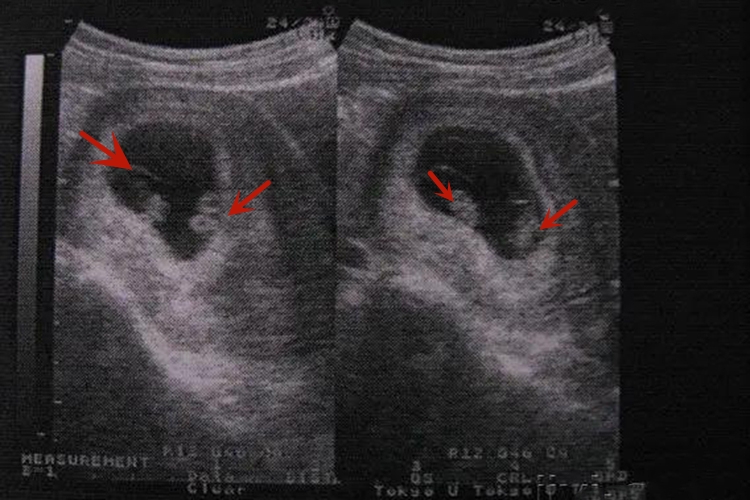

双胞胎30天B超一般还看不出来。孕妇进行B超检查,最早在怀孕30天时可发现妊娠囊,但只是部分孕妇能够发现,而且只能确定是早孕,不能确定是单胎还是双胞胎。一般需要等到6-7周,此时进行B超检查可以确定是单胎还是双胞胎,怀双胞胎者可发现宫腔内有2个妊娠囊,或者1个妊娠囊里有2个胚胎,即异卵双胞胎以及同卵双胞胎。